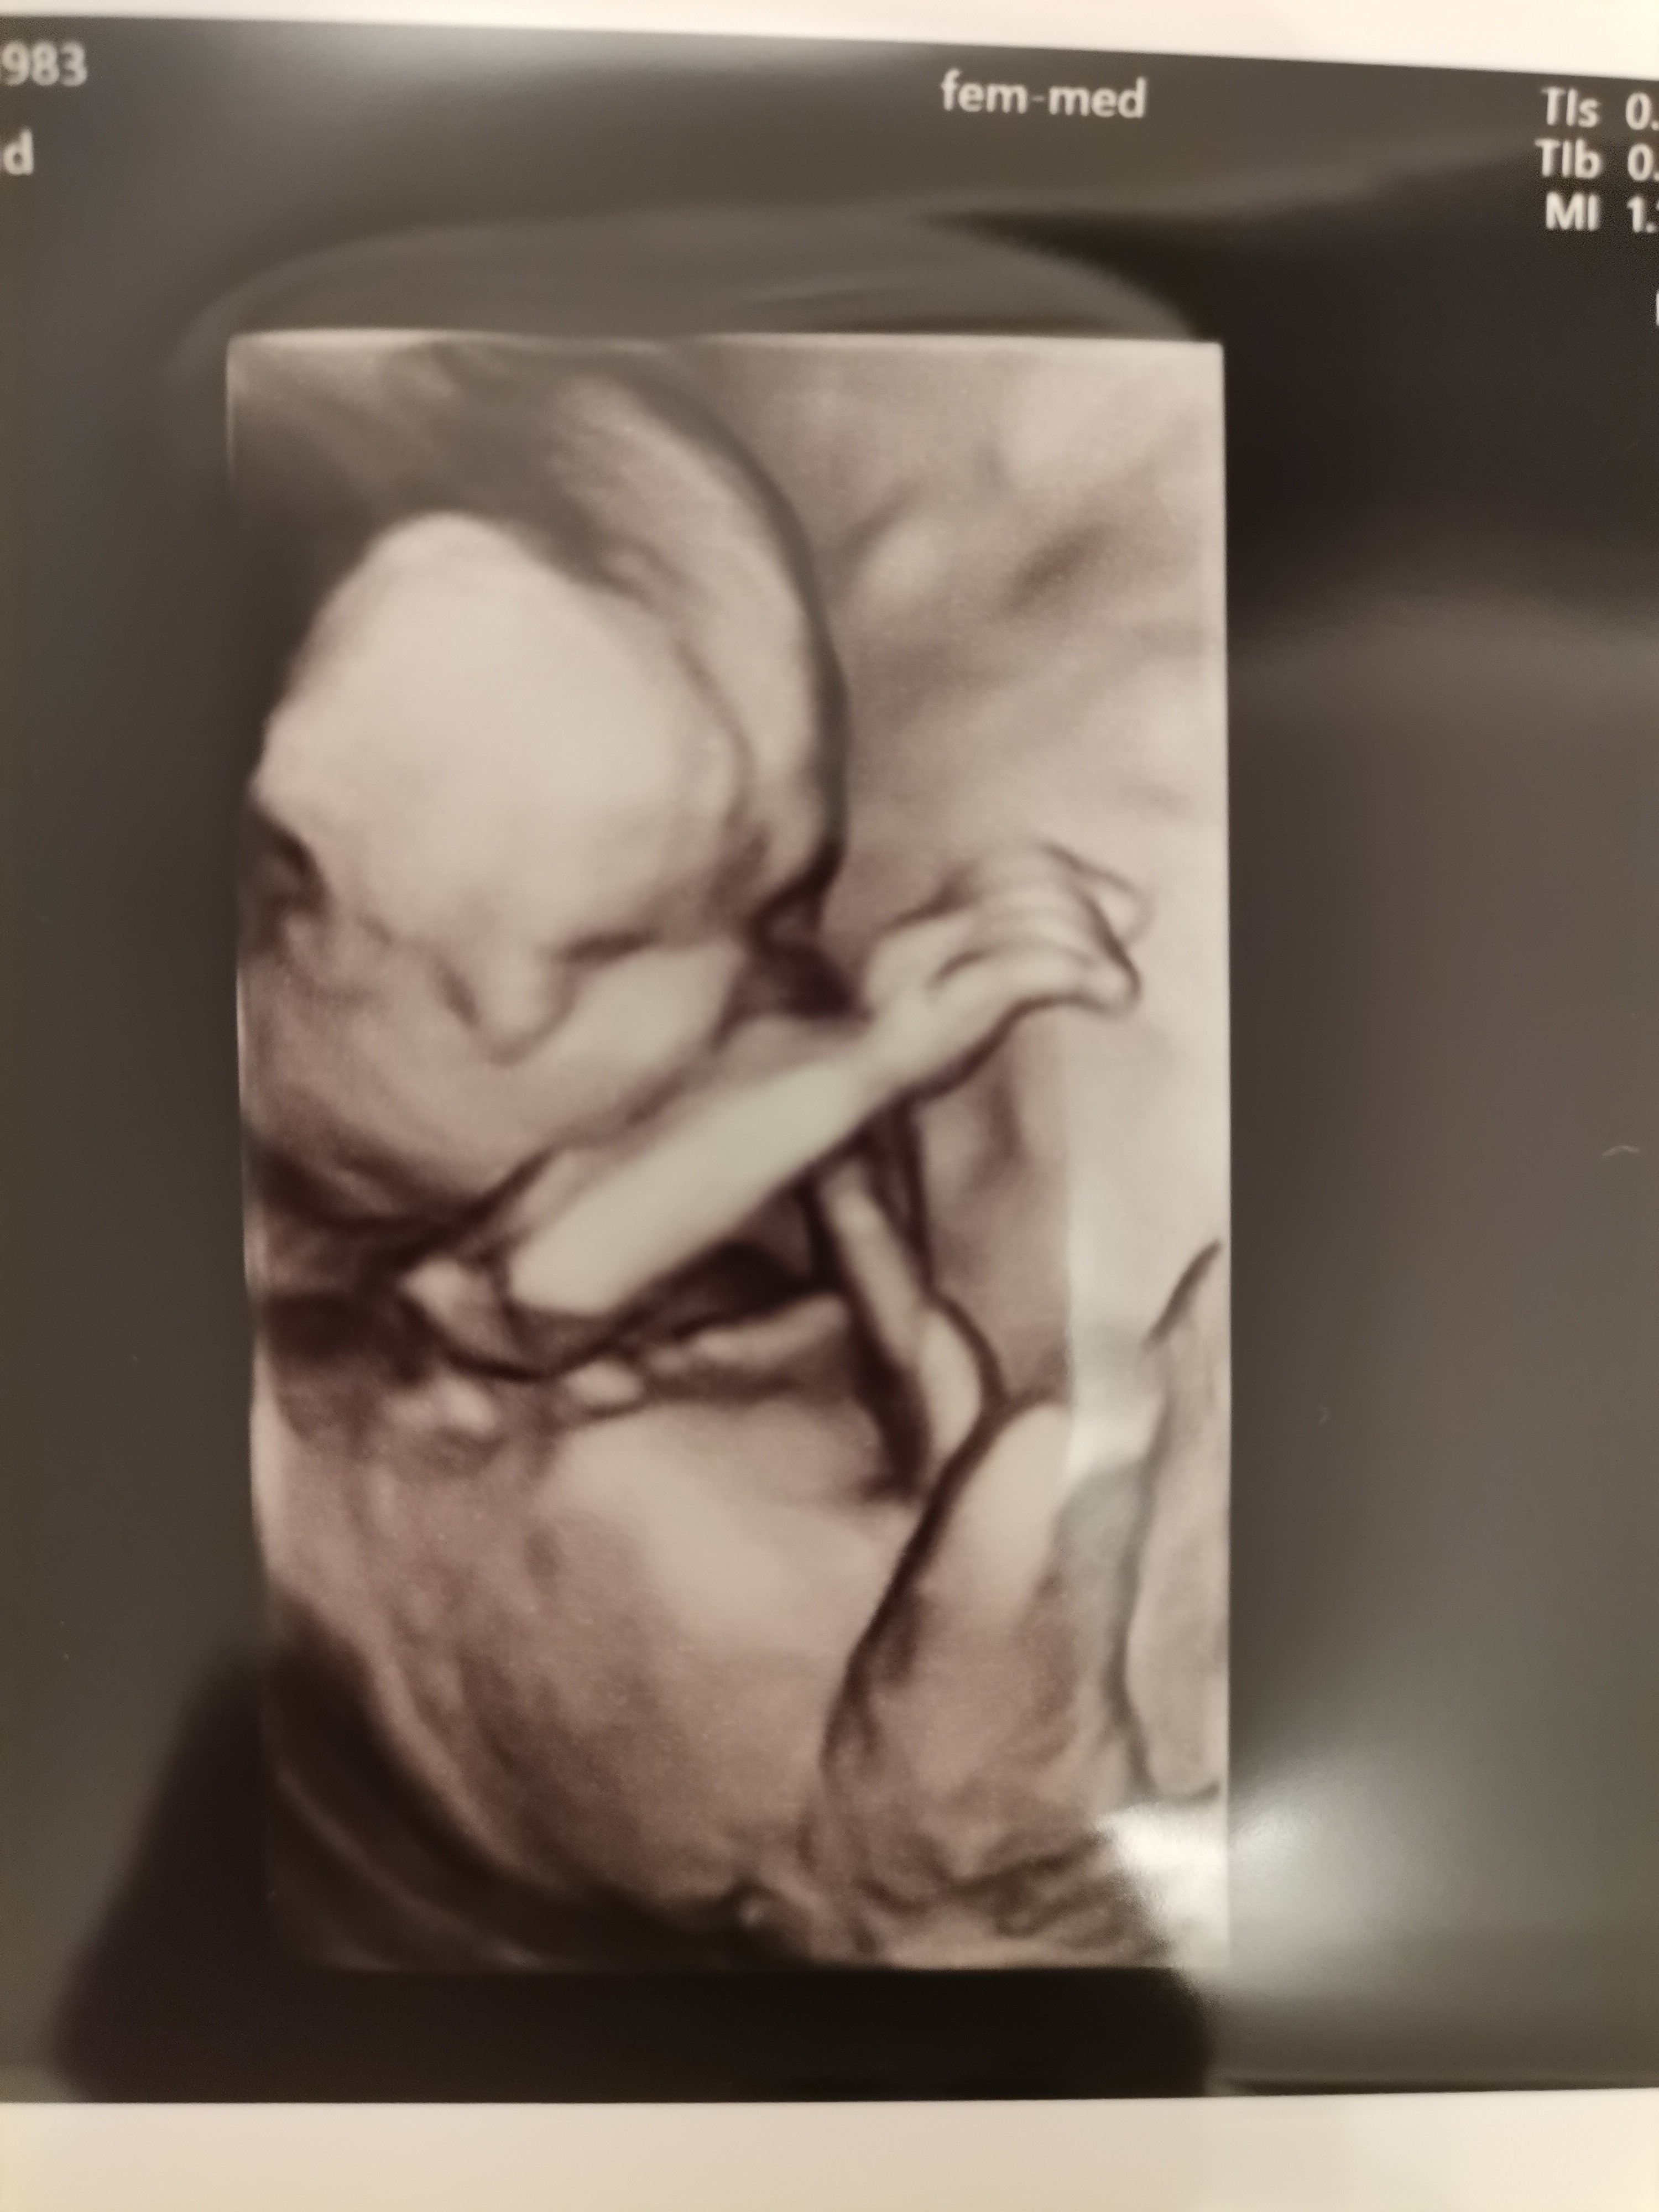

• IMG_20211018_205239.jpg

IMG_20211018_205239.jpg

1,2 MB · Wyświetleń: 96